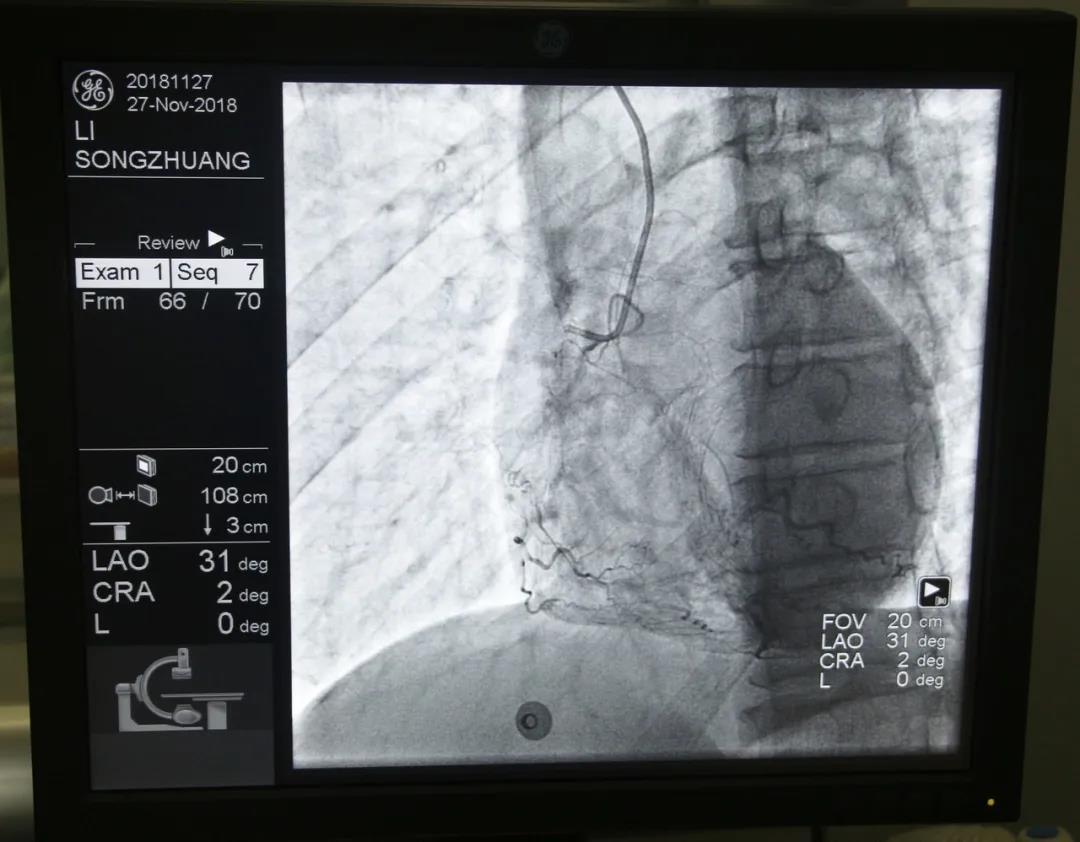

心內(nèi)科醫(yī)務人員冠狀動脈造影中

“冠狀動脈造影”即“冠脈造影”,是診斷冠心病的一種常用方法,作為一種有創(chuàng)診斷技術,它被稱為診斷冠心病的“金標準”。心內(nèi)科融無創(chuàng)與有創(chuàng)協(xié)同治療為一體,硬件設施齊全,配有美國GE大C型臂數(shù)字減影X線造影機,心臟臨時起搏器、床旁監(jiān)護儀、除顫儀、自動分析心電圖等,設有心臟重癥監(jiān)護室(CCU),擁有1個獨立導管室,設有心內(nèi)科??崎T診、心內(nèi)科病房(現(xiàn)有床位71張)、心血管無創(chuàng)檢查室、心電圖室等部門。科室現(xiàn)已熟練開展冠狀動脈造影技術,為心血管疾病患者帶來了福音。